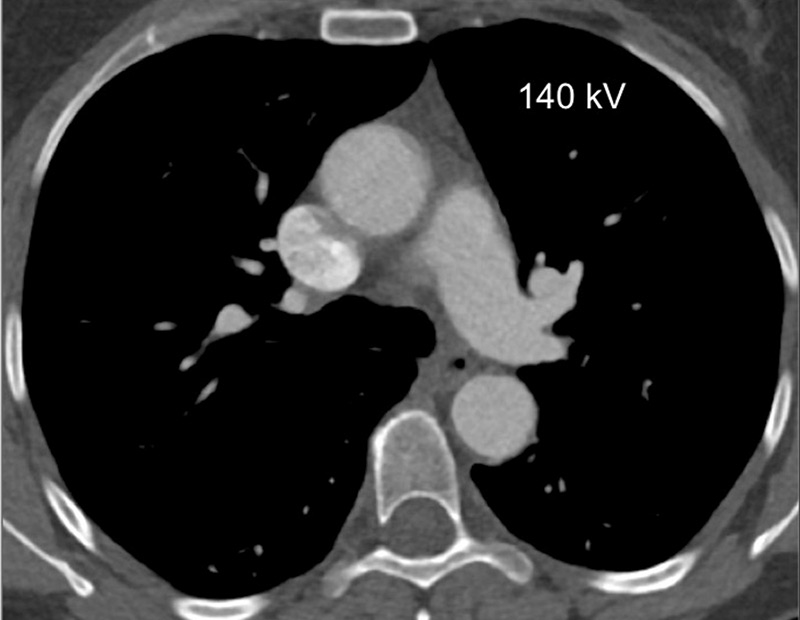

Because of the attenuation properties of iodine at two different photon energies (80 and 140 kV), a dual-energy technique can generate pulmonary blood volume maps and quantify the iodine concentration in the parenchyma. It has been demonstrated that the local distribution of iodine contrast medium correlates well with pulmonary perfusion [18]. The generated pulmonary blood volume maps are combined with mediastinal images to permit simultaneous analysis of the grey-scale vasculature and colour-scale parenchymal perfusion, with parenchymal images (fig. 1). Furthermore, the iodine concentration in the lung allows an objective and quantitative analysis.

Figure 1

Technical principles. The dual-energy system with two X-ray tubes permits simultaneous 80 (A) and 140 kV (B) image acquisition in order to generate an iodine map (C) fused with mediastinal reconstructions (D).